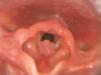

Los papilomas laríngeos se objetivaron con fibrolaringoscopia, y se realizó exéresis (fig. 1) mediante microcirugía endolaríngea. Recibieron tratamiento coadyuvante intraoperatorio con cidofovir intralesional en al menos una ocasión en 4 de los 6 casos. El caso 2 recibió además propranolol vía oral diariamente durante un año. La anatomía patológica fue concordante con papilomatosis, y se identificó en los casos 2 y 3 el serotipo VPH-11 y en el caso 6 VPH-6.